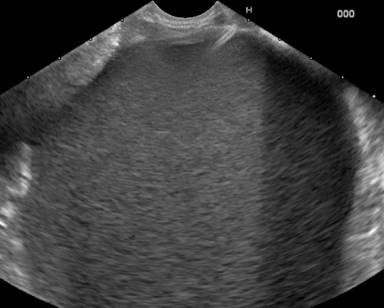

Two months later he had intermittent abdominal pain relieved with analgesics and 4 months later, he presented with severe pain and fever of 15-day duration. On evaluation he was febrile, with tender upper abdomen and elevated leukocyte count (15,900 mm-3). CECT abdomen and EUS revealed a 9x8 cm well defined collection anterior to body and tail of pancreas as well as extending into the lesser sac (Figure 2). Rest of the visualized pancreas had no calcifications, ductal dilatation or any other features of chronic pancreatitis. In view of persistent pain, fever and elevated leukocyte count, a possibility of infected pseudocyst associated with acute pancreatitis was considered and endoscopic cystogastrostomy was done. During the procedure nodularity, grooving and scalloping of duodenal folds was observed (Figure 3) which on histology showed subtotal villous atrophy (Figure 4). IgA anti-tissue transglutaminase levels (Anti tTG, Celekey Germany, ELISA; reference range: 0-15 U/mL) were ordered and were found to be elevated (>300 U/mL). A diagnosis of celiac disease was made and he was started on gluten free diet. Four weeks later he underwent endoscopic retrograde pancreatography which showed evidence of disruption in the tail region. Pancreatic sphincterotomy was done and a 5 Fr x 12 cm pancreatic stent placement. Two months later the stent was removed and a subsequent ultrasound abdomen showed no recurrence of pseudocyst. He has remained well for the last 6 months with no recurrence of abdominal pain.

Figure 2. Linear echoendoscopic image showing a 9x8 cm pseudocyst with echogenic contents with well-defined walls. |